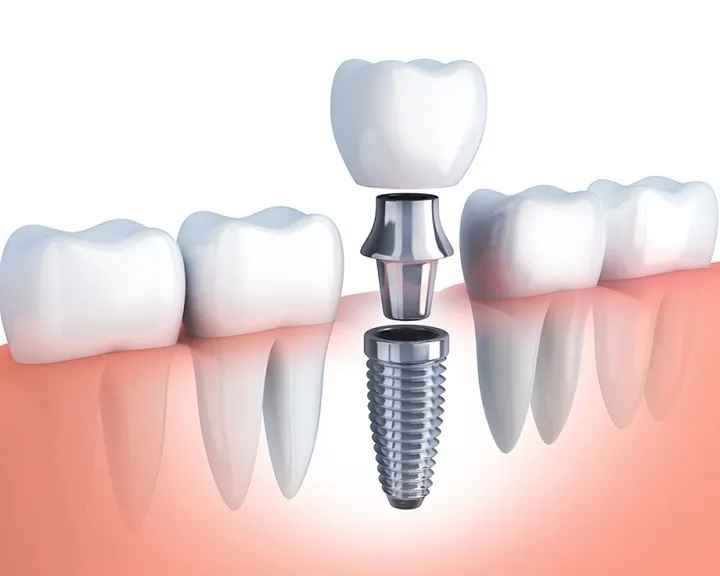

Khi lợi bị tụt nghiêm trọng ở nhiều răng, phần lợi bị viêm đỏ nặng. Lúc này chân răng lộ ra ngày càng nhiều thì ngoài việc tới nha khoa lấy cao răng thì phẫu thuật là cách điều trị tốt nhất đối với trường hợp này. Có 3 phương pháp phẫu thuật tụt nướu với các ưu nhược điểm như sau:

- Phẫu thuật vạt tại chỗ tụt nướu. Phương pháp này được chia nhỏ thành các phương pháp nhỏ. Ví dụ như phẫu thuật trượt về phía cổ răng, trượt bên, nhú lợi kép, …

- Phẫu thuật sử dụng mô ghép rời tự thân. Đây là kỹ thuật sử dụng mô ở phần khác cấy vào phần bị tụt nướu. Nó được chia thành các phương pháp nhỏ. Ví dụ như ghép mô liên kết dưới biểu mô, ghép lợi tự do tự thân,…

- Phẫu thuật sử dụng màng nhân tạo kết hợp với vạt tại chỗ. Ví dụ như dùng biểu mô không tế bào, tái sinh mô,…

Tuy nhiên, mỗi phương pháp sẽ có đặc điểm khác nhau. Bạn cần phải trao đổi với bác sĩ để được thăm khám và tư vấn chính xác. Nếu bạn còn gặp phải các vấn đề khác về răng miệng, cần phải điều trị lần lượt từng vấn đề sau đó chăm sóc và phục hồi dần.